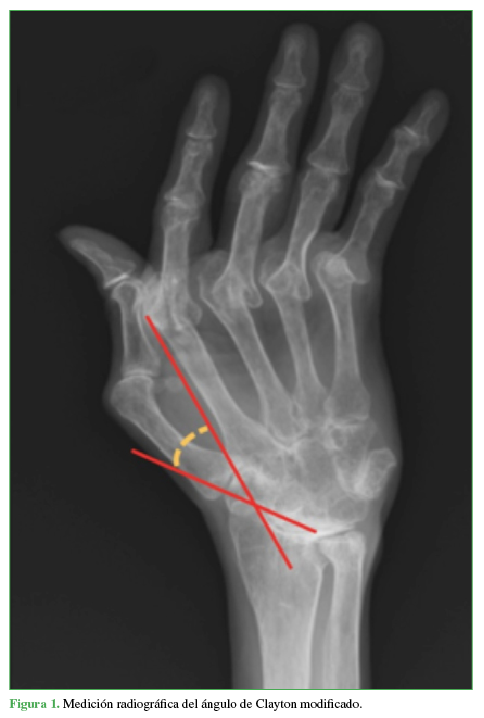

Se registraron variables demográficas, como edad y sexo, el lado afectado y la duración del seguimiento. Se evaluaron las radiografías de mano, de frente, preoperatorias y posoperatorias, midiendo el ángulo de Clayton7 (Figura 1) definido como aquel que se forma entre el eje del segundo metacarpiano y la línea de inclinación radial en la superficie articular de la muñeca en la radiografía anteroposterior.

Los pacientes fueron divididos en dos grupos: con transferencia del ERLC al ECC (grupo A) y sin transferencia (grupo B). En cada grupo, se calculó la corrección del ángulo metacarpiano-radial (ángulo de Clayton) comparando las medidas preoperatorias y las del último control, y se compararon los resultados obtenidos entre ambos grupos.